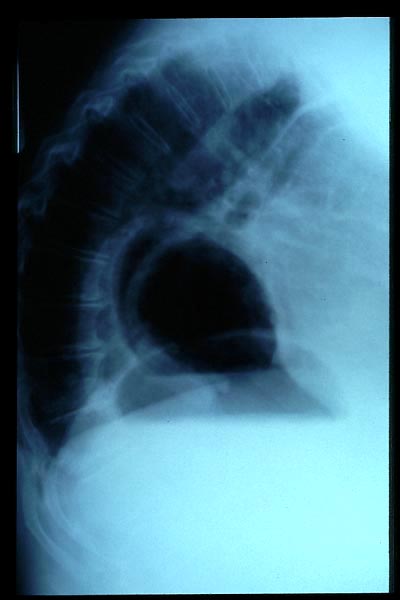

Deformidad torácica.